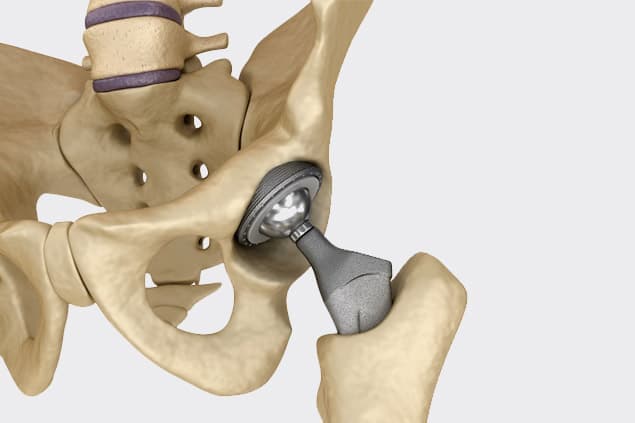

Total hip replacement (THR), on the other hand, involves replacing both the femoral head and the acetabulum with prosthetic components. This comprehensive approach is often necessary for individuals suffering from severe osteoarthritis, rheumatoid arthritis, or other degenerative conditions that affect both parts of the hip joint. During a total hip replacement, the surgeon removes the damaged cartilage and bone from both the femoral head and the acetabulum, replacing them with artificial components made of metal, ceramic, or plastic. The prosthetic components are designed to mimic the natural movement of the hip joint, providing significant pain relief and improved mobility.

Total hip replacement surgery involves the use of various materials to create prosthetic components that replace the damaged parts of the hip joint. These materials are carefully selected for their durability, biocompatibility, and ability to replicate the natural movement of the hip. The primary components of a total hip replacement include the femoral stem, femoral head, acetabular cup, and a liner that fits within the acetabular cup.

The femoral stem, which is implanted into the thigh bone (femur), is typically made of metal alloys such as titanium or cobalt-chromium. Titanium is favored for its lightweight nature, strength, and excellent biocompatibility, allowing it to integrate well with the surrounding bone. Cobalt-chromium alloys are known for their high wear resistance and strength, making them suitable for the demanding environment of the hip joint.

The femoral head, which replaces the ball of the thigh bone, can be made of either metal or ceramic. Ceramic femoral heads are becoming increasingly popular due to their smooth surface, which reduces friction and wear against the acetabular cup. Metal femoral heads, often made of cobalt-chromium, are also commonly used for their durability and wear resistance.

The acetabular cup, which replaces the hip socket, is usually made of metal alloys such as titanium or cobalt-chromium. To reduce wear and provide a smooth articulation surface, the acetabular cup is often lined with a polyethylene (plastic) liner or a ceramic liner. Highly cross-linked polyethylene liners have improved wear resistance compared to traditional polyethylene, making them a popular choice for hip replacements.